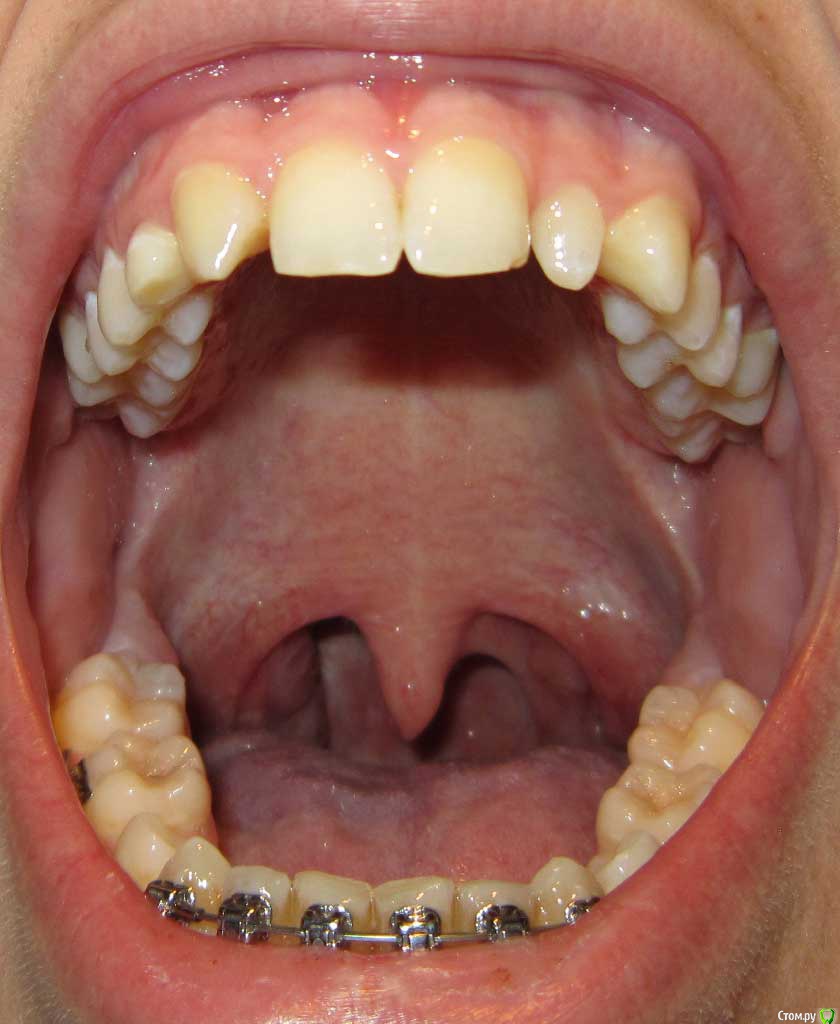

Сейчас мне 17 лет. На лечении у ортодонта с августа 2013 года. Удалили молочные пятерки и стали сдвигать шестерки к передним зубам. На верхнюю челюсть она ставить брекеты не стала. Осенью 14 года врач ушла в декрет.

Пришел новый врач который предложил все сделать несколько иначе: поставить брекеты на обе челюсти, все выравнять и освободить место под будущие импланты: вместо пятерок снизу и второго слева резца сверху -, а пока на их место поставить коронки. Также врач назвал сроки: около 1 года.

Сверху слева отсутствует зачаток второго резца, вместо него находится клык и молочный зуб левее. Внизу нет зачатков пятерок.